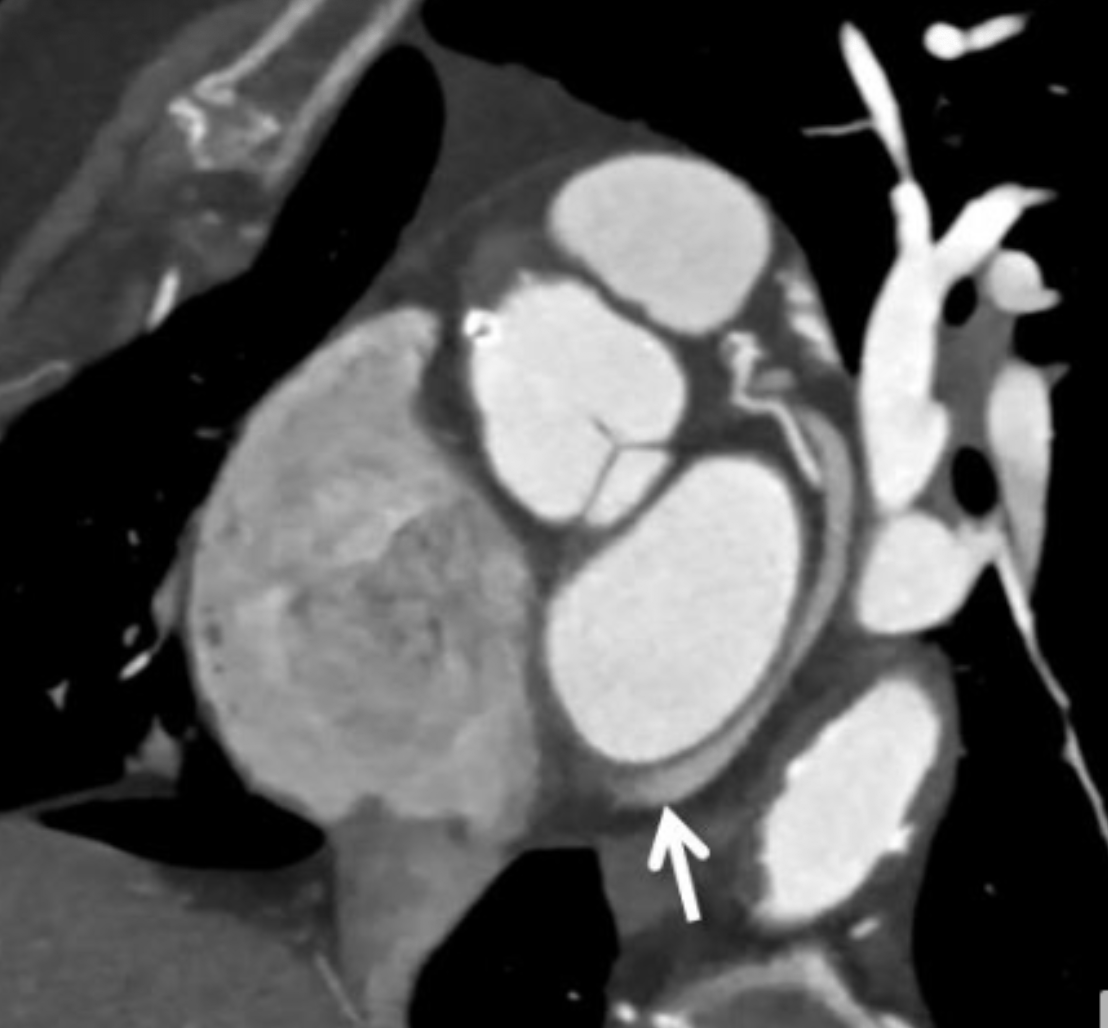

Describe the CT scan protocol/view:

Oblique MIP of the RCA

Describe the RCA findings in this image:

Cardiac Motion Artifact